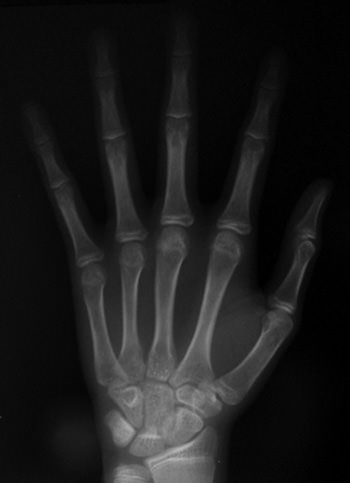

Se indican radiografías periapicales de la zona para observar la anatomía de las coronas y el nivel de la cresta ósea respecto a la línea amelocementaria y radiografía de la mano y muñeca para determinar la madurez esquelética del paciente. Constatamos que el paciente ha alcanzado su máximo crecimiento óseo y por lo tanto es factible la realización de un tratamiento quirúrgico. Foto 2 y 3)

Foto 3

Radiografía de la mano y muñeca